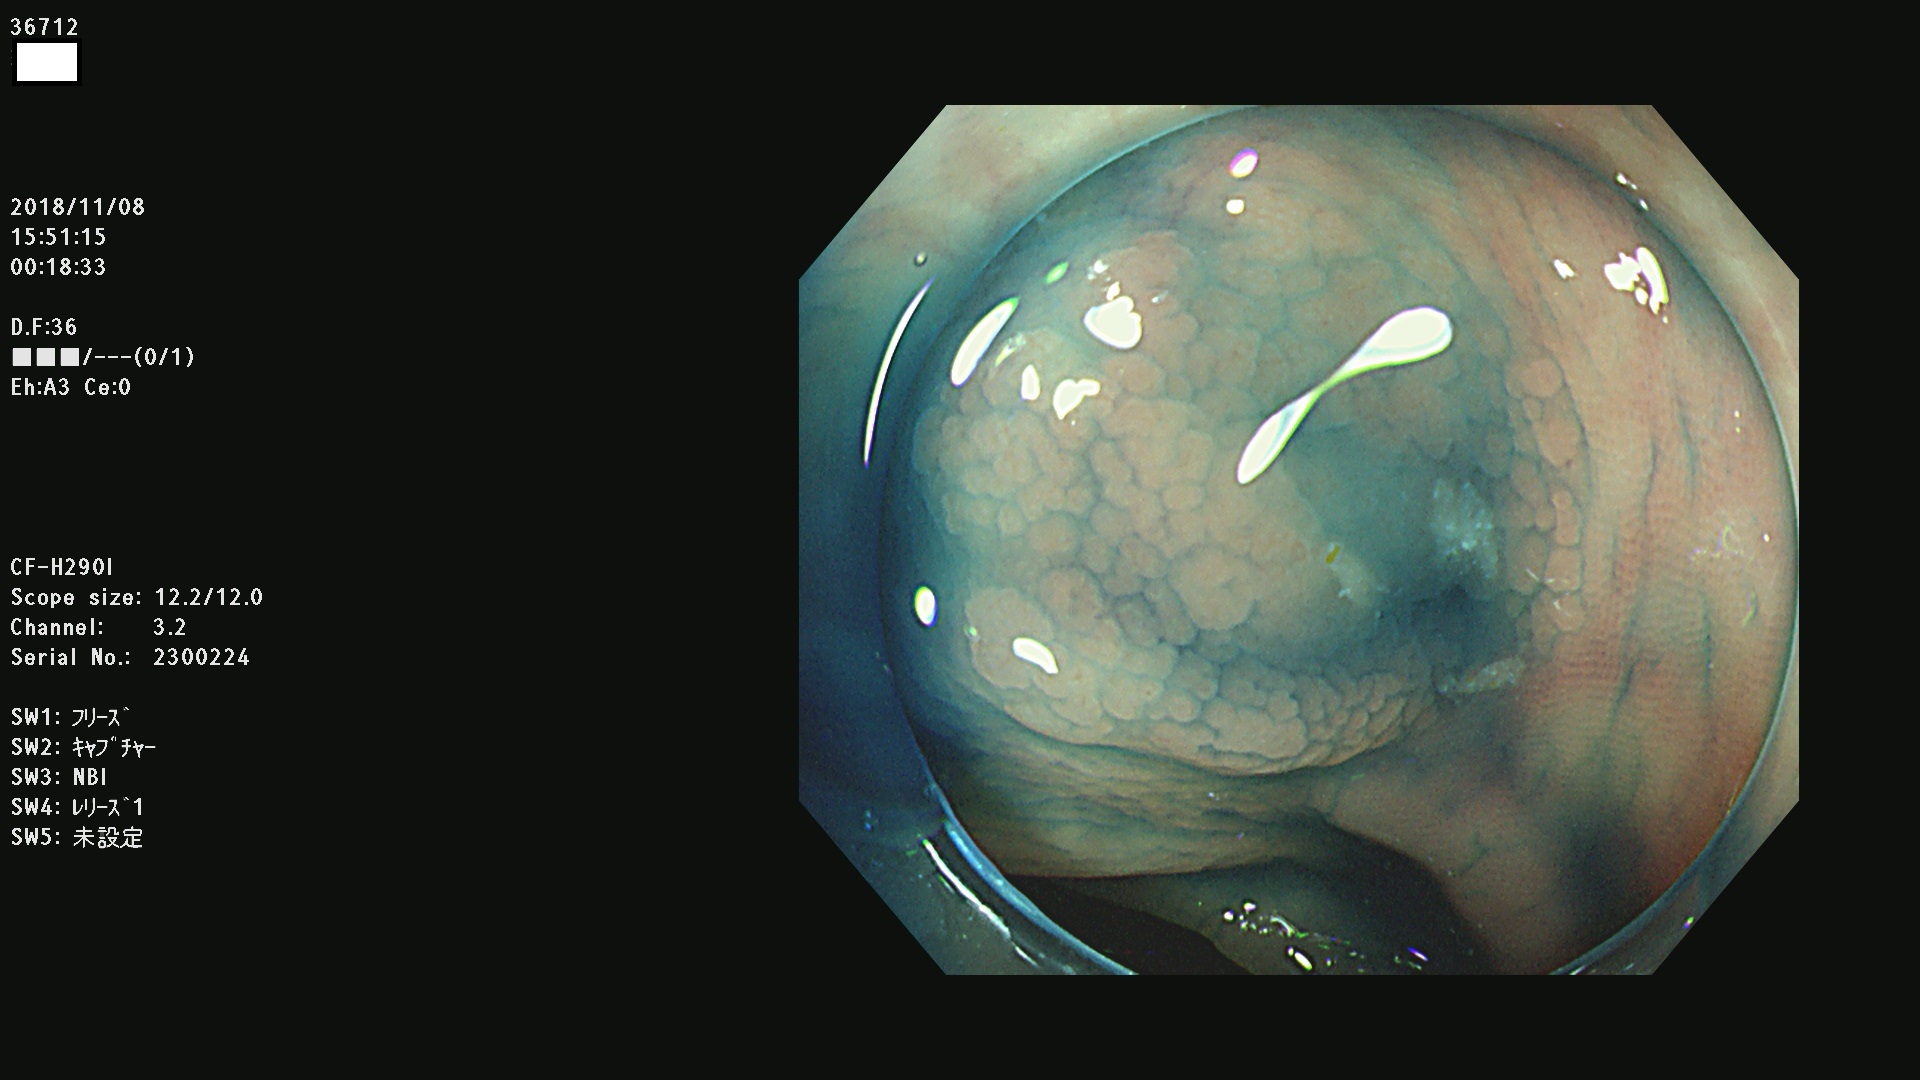

36700 36701 36702 36704 36705 36707 36708 36710 36712(SSAPのみ) 36714 36715 36716 36717 36718 36721 36723 36724 36730 36731 36732 36734 36735 36736 36738 36739 36742 36744 36745 36746 36749 36752(SSAPのみ) 36754 36756 36758 36759 36760 36731 36732 36734 36737 36738 36739 36771(SSAPのみ) 36772 36773 36774 36775 36776 36777 36780 36781 36783 36785 36786 36788 36790 36792 36794 36797 36798

発見困難で危険性の高い平坦型病変(上記100名より抽出)